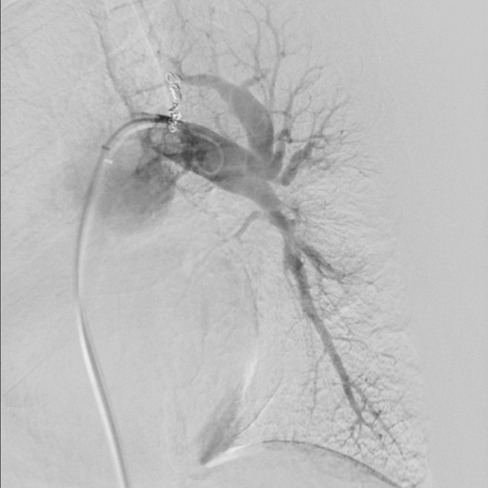

第四次(2021.7)拟行肺动脉支架植入术入院,于2021-7-7行右心导管检查+肺动脉造影+肺动脉支架植入术:支架植入前测量右房压为25/9(15)mmHg,右心室压为55/2(19)mmHg,肺动脉压为55/29(38)mmHg,CO 2.2 L/min,PVR 11.8WU。测量左肺下叶肺动脉近端压力51/23(32)mmHg,远端压力为15/11(12)mmHg,右肺下叶肺动脉近端压力52/20(31)mmHg,远端压力为11/8(9)mmHg,于右肺动脉基底干狭窄处植入PLU-STENT M30支架一枚,测量病变远端压力为51/23(32)mmHg,未见明显压差。

肺动脉支架植入术